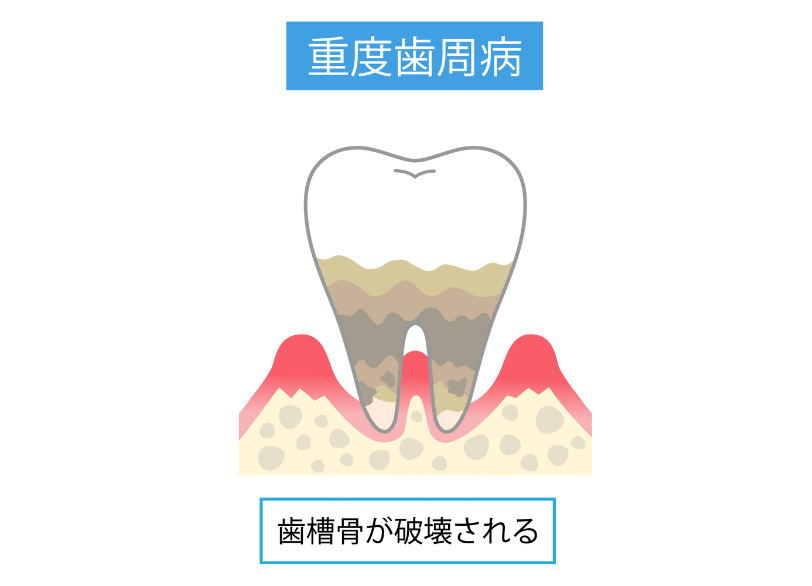

歯槽骨(歯を支える骨)の破壊

歯周病が本当に恐ろしいのは、炎症が歯ぐきだけでなくその下にある歯を支える骨(歯槽骨)にまで及ぶ点です。

歯周病菌によってこの大切な骨が少しずつ溶かされ、吸収されていきます。

建物の土台が蝕まれていくのと同じで、歯を支える土台がなくなれば歯はグラグラと動揺し始め、終的には支えを失って抜け落ちてしまうのです。

一度溶けてしまった骨は基本的には元に戻ることはありません。